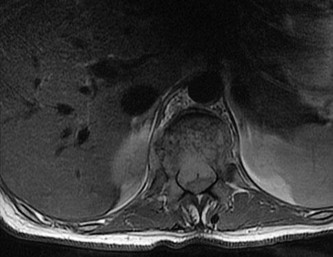

Question 9

During secondary fracture healing in the setting of relative stability, the fracture callus progresses through an endochondral ossification pathway. Which of the following transcription factors is fundamentally essential for the differentiation of mesenchymal stem cells into chondrocytes to form the initial soft callus?

Explanation

Secondary fracture healing relies heavily on endochondral ossification, beginning with a cartilaginous soft callus. Sox9 is the master transcription factor required for chondrocyte differentiation. Runx2 and Osterix are key transcription factors for osteoblast differentiation (membranous ossification and hard callus formation). NFATc1 is critical for osteoclastogenesis. Beta-catenin is a key component of the Wnt signaling pathway, which promotes osteoblastogenesis while actually suppressing chondrogenesis.